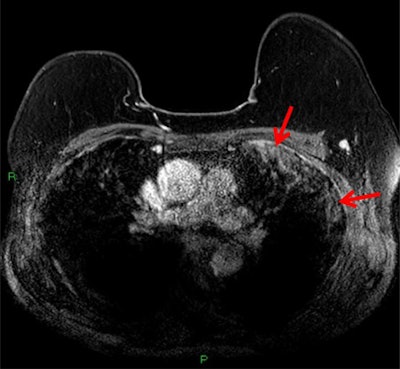

But the breast cancer wasn't the patient's only notable MRI finding. The reading radiologist also spotted incidental findings in the pulmonary space on the patient's MRI, including abnormal subpleural high T2 signal intensity in the lung periphery and enhancement in subpleural regions on postcontrast, fat-saturated T1-weighted images.

"Given the high prevalence of COVID-19 infection in the local community at the time, concern was raised that the incidental lung findings may be secondary to positive COVID-19 status," the authors wrote.

While COVID-19 findings are well-documented for CT and chest radiography, the disease's presentation is not as well understood on MRI. Other reports have said COVID-19 can present similarly to other forms of pneumonia, including nonspecific high T2 signal intensity with enhancement on postcontrast T1 imaging.